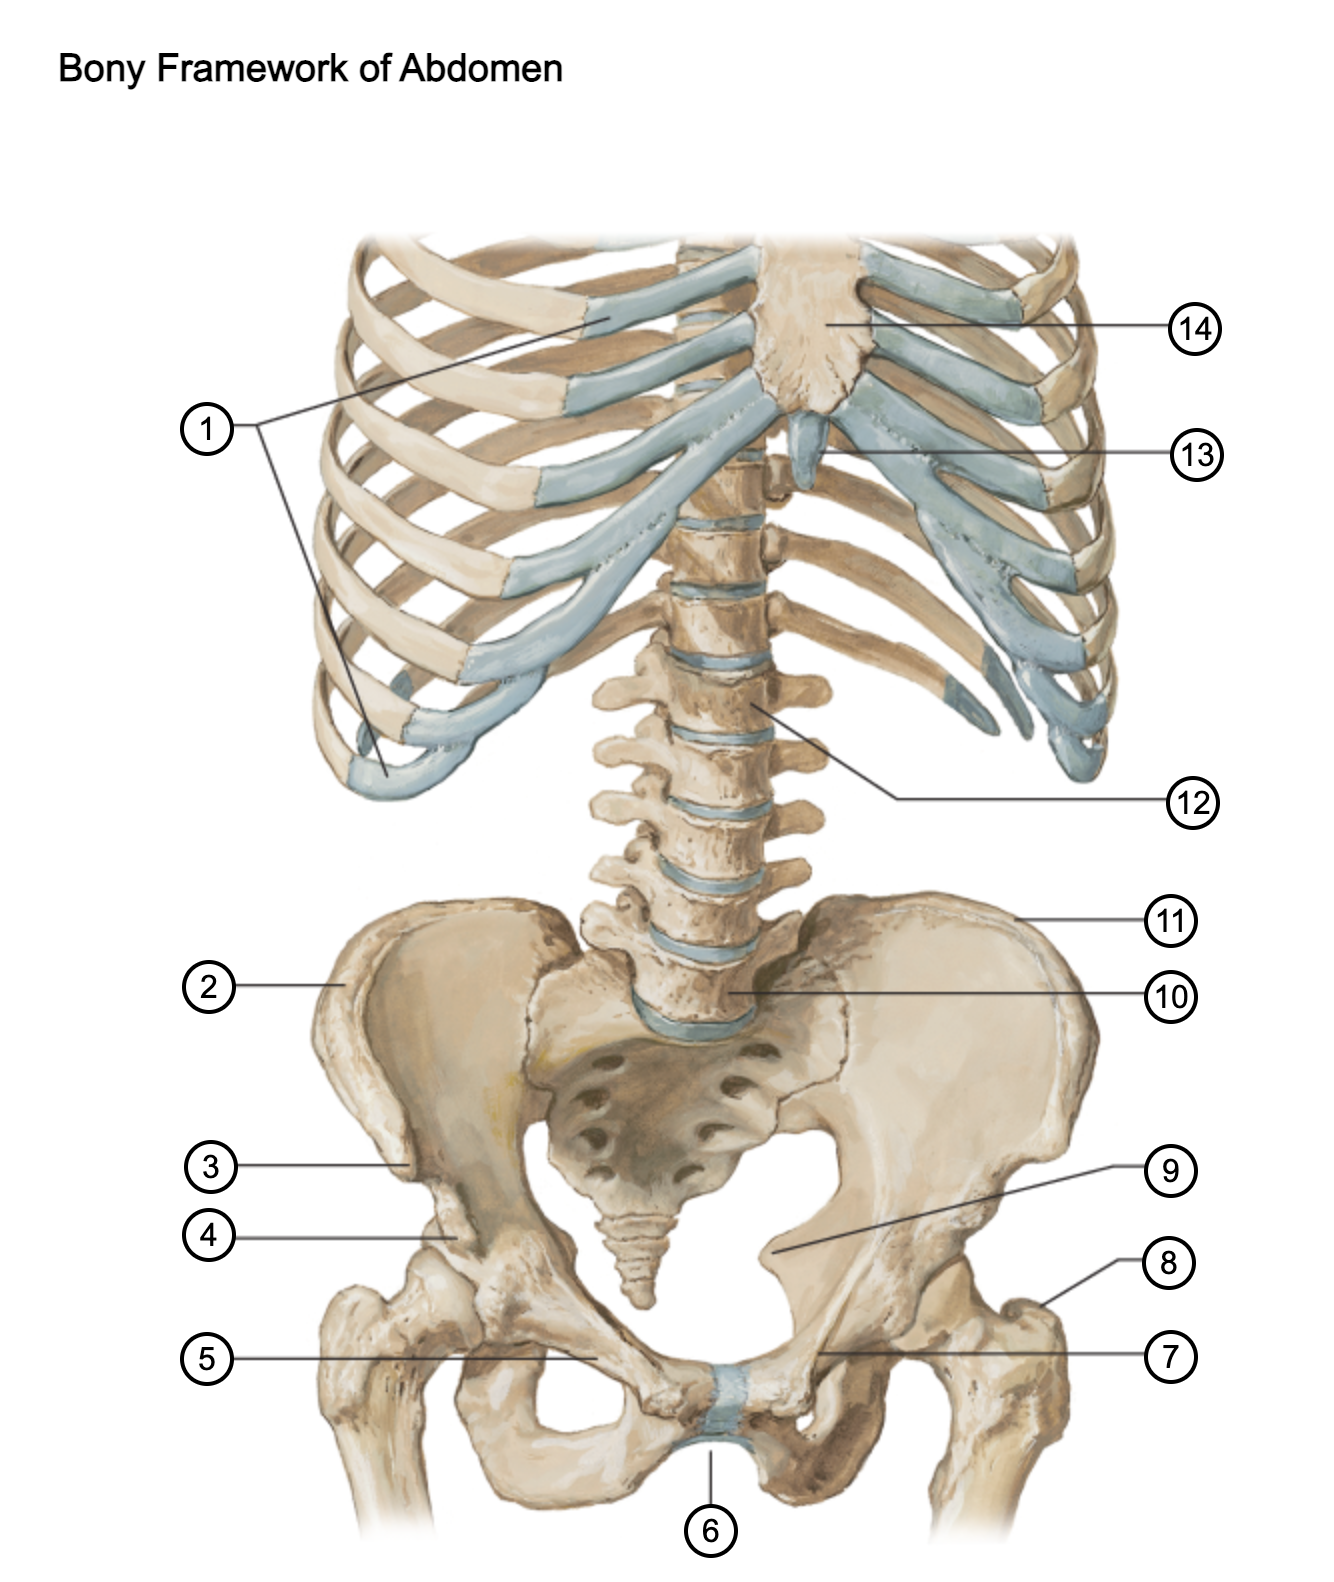

1

costal cartilages

2

iliac crest

3

anterior superior iliac spine

4

anterior inferior iliac spine

5

superior pubic ramus

6

pubic arch

7

pecten pubis

8

greater trochanter

9

ischial spine

10

L5 vertebra

11

iliac crest

12

L1 vertebra

13

xiphoid process

14

body of sternum